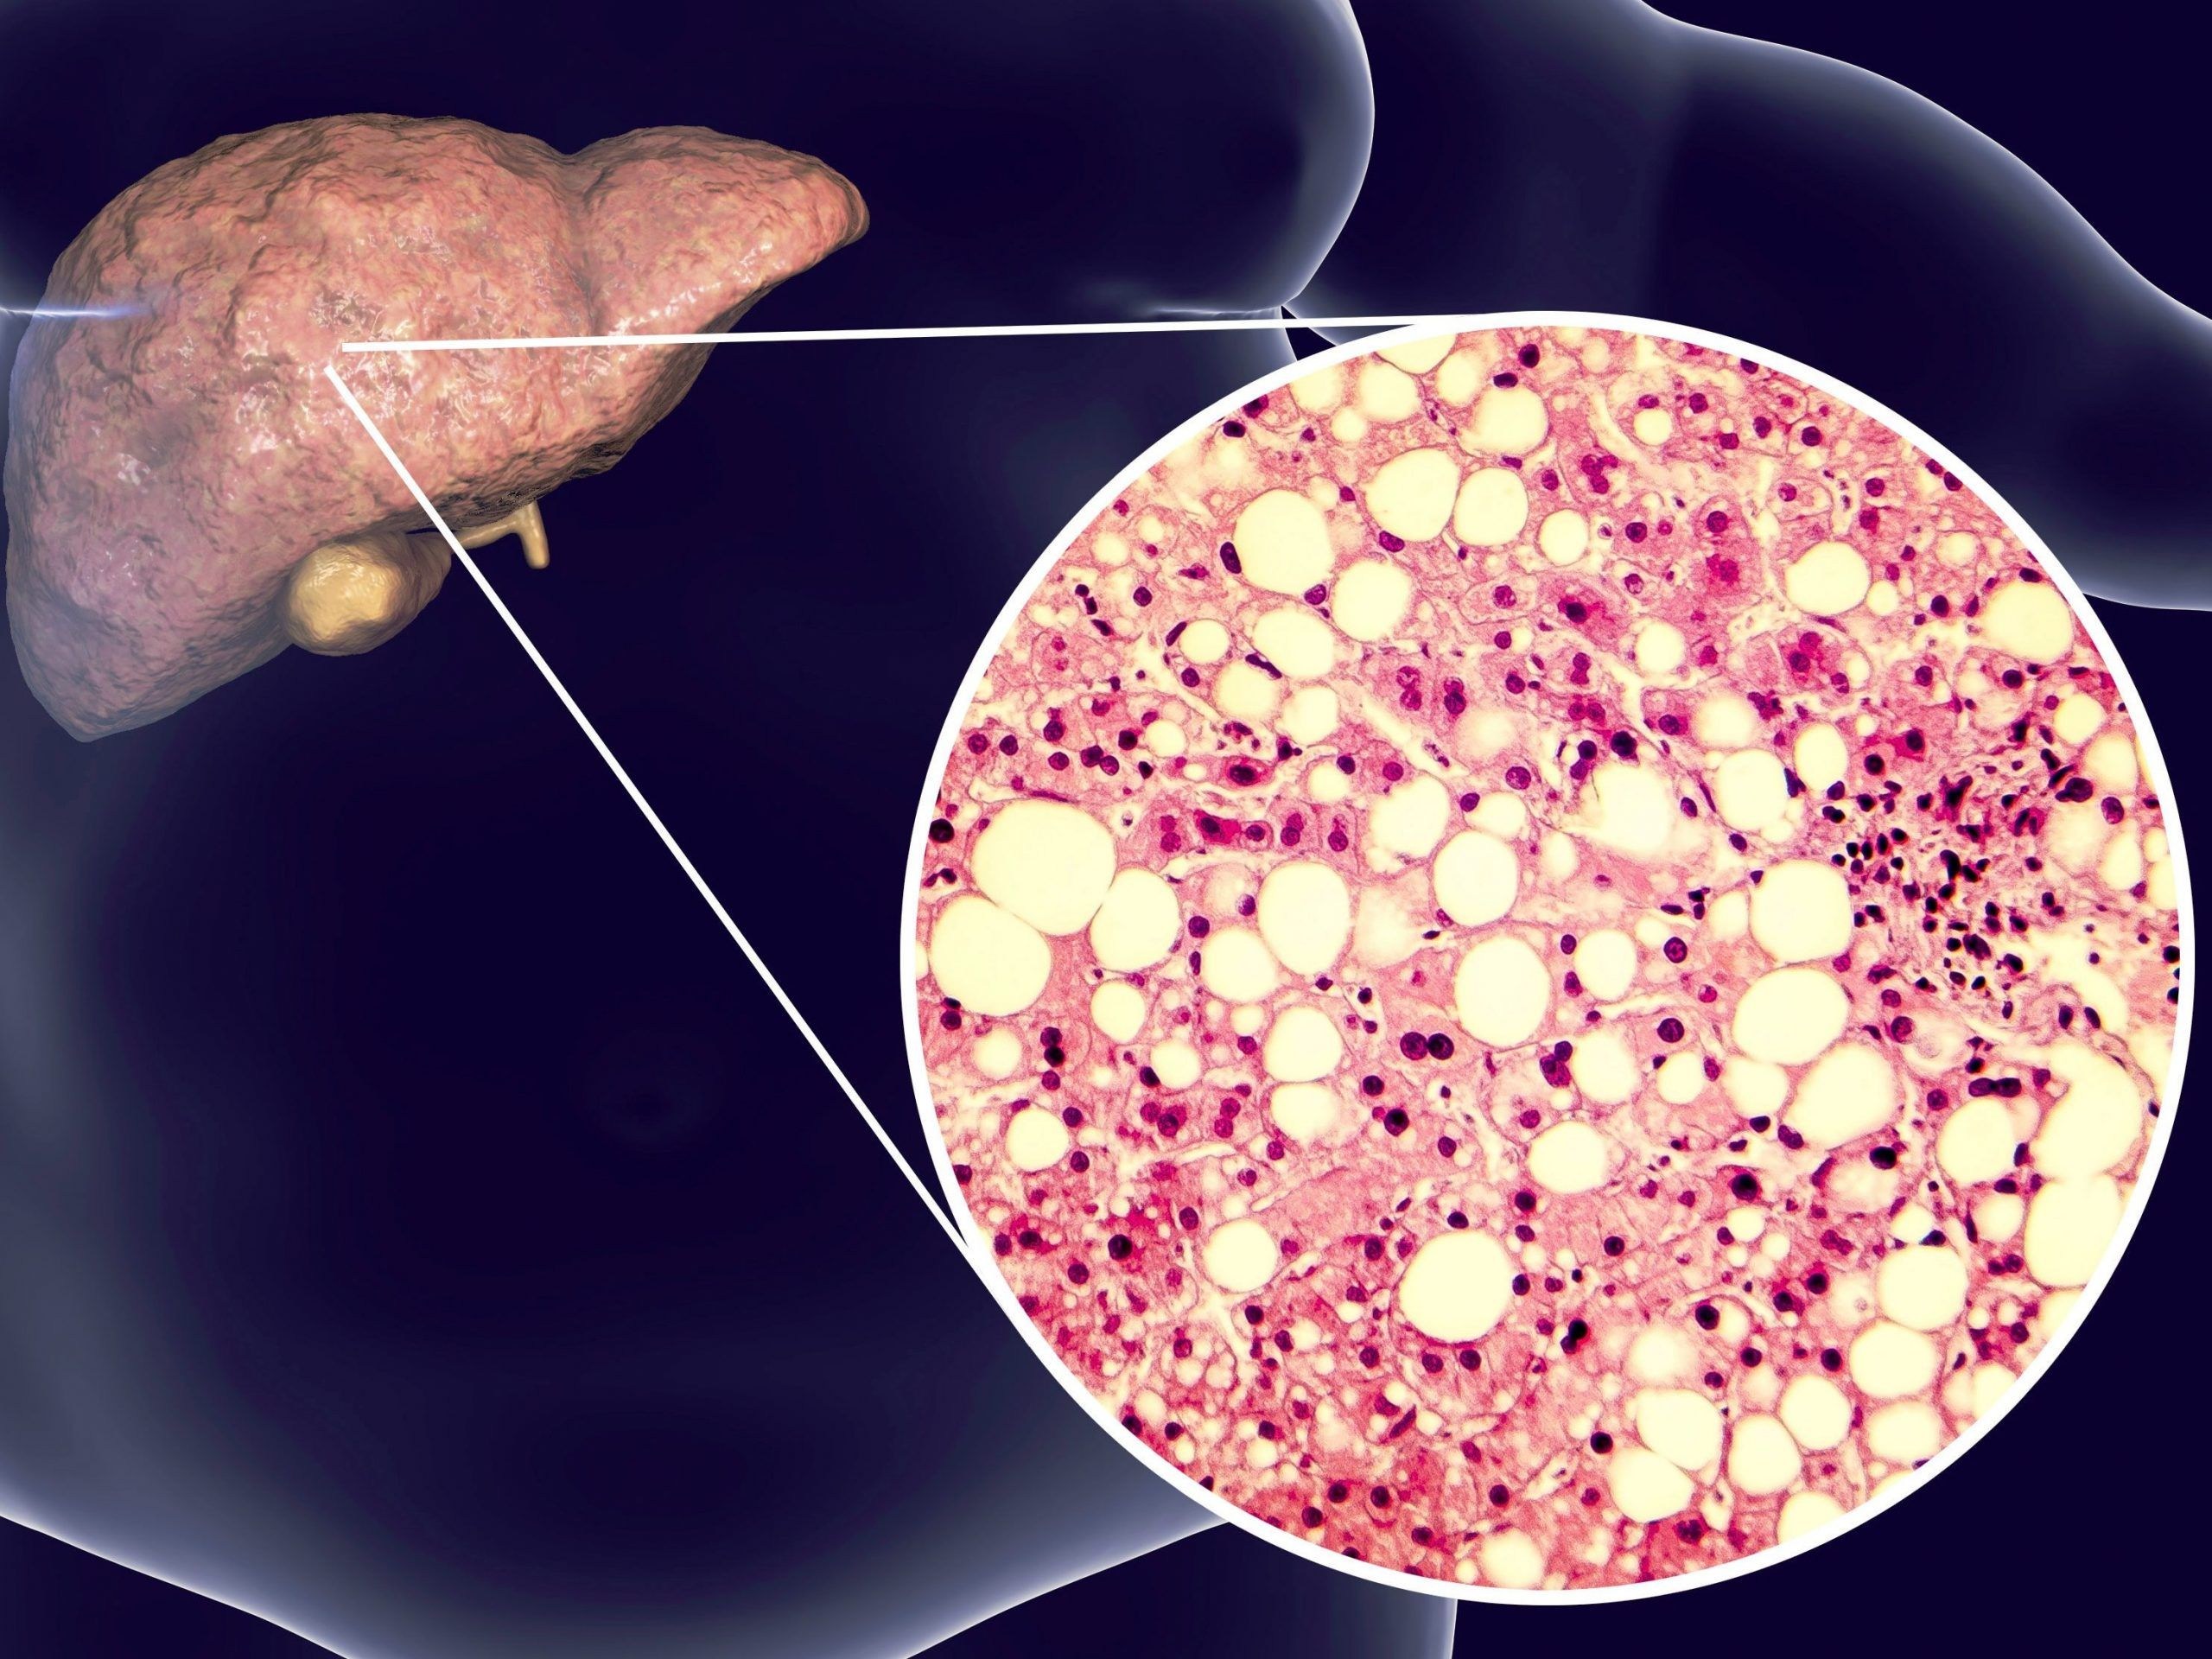

Практические советы по лечению ожирения печени в домашних условиях

Узнайте, как можно эффективно и безопасно лечить ожирение печени в домашних условиях с помощью простых рекомендаций и советов. Избавьтесь от этого заболевания и улучшите свое здоровье с легкостью.

Жировой ГЕПАТОЗ : причины, симптомы, ДИЕТА и ЛЕЧЕНИЕ. Ожирение печени: что делать.